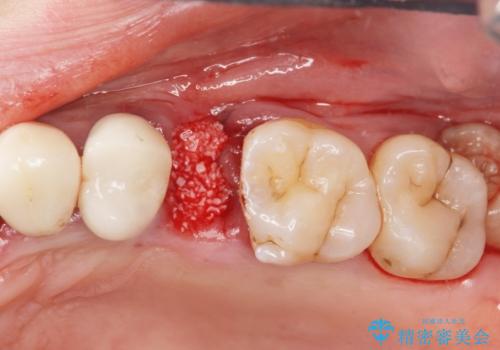

X線、歯周組織検査の結果、残すことができない歯周病の進行が左上小臼歯に認められました。

抜歯後は、インプラントではなくブリッジを選択されました。

最終的なブリッジの清掃性を高めるため、歯ぐきのボリュームがこれ以上減少しないよう抜歯時に歯槽堤保存術を行うような工夫をしています。